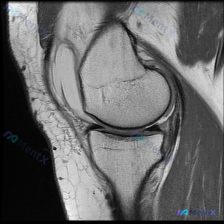

今天看到一个很有代表性的读片问题,整理一下思路分享给大家。 病例/问题背景 问题:针对一张标注怀疑「软骨异常」的膝盖MRI T1加权轴位图像,描述可见的视觉表现。 --- 影像基础信息 图像为单张膝关节水平面T1加权成像(T1WI),这个序列的基本信号特点是:骨髓、皮下脂肪呈高信号(亮),肌肉呈中等...